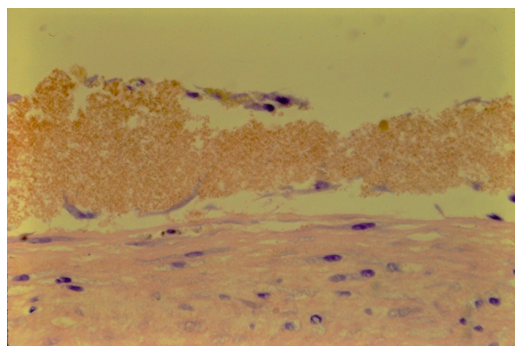

A biopsy of the regenerated tissue on the meniscus shows an avascular cellular matrix on the intact and viable host meniscus (Figure 3). High power photomicrograph of the regenerated tissue shows no vascularity only cellular proliferation.

Nineteen of the 31 specimens subject initially to only the patient’s synovial fluid showed repair cells on the surface (Figure 5). In five instances there was cellularity in or covering the core defect (Figure 7a). In mixture of blood and synovial fluid there was greater amount cellularity in the clot of the core defect (Figure 7b).

Figure 7: a: Photomicrograph of minimal cellularity attached to the surface of the disrupted meniscus tissue adjacent to the core lesion. There was occasional meniscal cell observed but no evidence suggesting cellular proliferation or continuity to the cellularity on the surface. b: Photomicrograph of abundant cellularity in the core defect in blood/synovial fluid environment.

The meniscal tissue remained viable in eighteen, hypocellular in 3, rare cells in 4 and no cells in 6 (dead). The absence of meniscal cells was not related to the presence of repair cellularity from the synovial fluid. In other words, repair cells existed even when the meniscus specimen was acellular, and presumable non-viable. Conversely the presence of cells in the meniscus substance did not insure existence of repair cells.